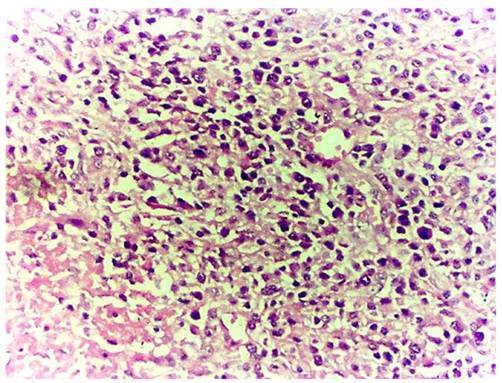

Figure 3

Infiltration of the lamina propria of the fallopian tube plicae with foamy histiocytes and chronic inflammatory cells (case 2).

Figure 4

Clusters of foam cells in the lamina propria of the fallopian tube in high power view (case 2).

Microscopic examination: The visibly-decreasing fallopian tube plicae were distended and covered by low-columnar glandular epithelium. There were infiltration by xanthoma cells admixed with inflammatory cells such as lymphocytes, plasma cells and neutrophils (Figures 3-4), accompanied with fibroplasia and vascular proliferation in the stroma. The xanthoma cells present either focally or in sheets, with no giant cells identified. A cyst-wall-like structure identified on the left ovary which measured 4 × 3 × 1.3 cm. The subsequent immunohistochemical stains showed CD68 positivity in the xanthoma cells, CD3, CD20, κ and λ were positive in the lymphocytes and pan cytokeratin was positive in the glandular epithelium. Pathological diagnosis rendered left xanthogranulomatous salpingitis and follicular cyst of left ovary.